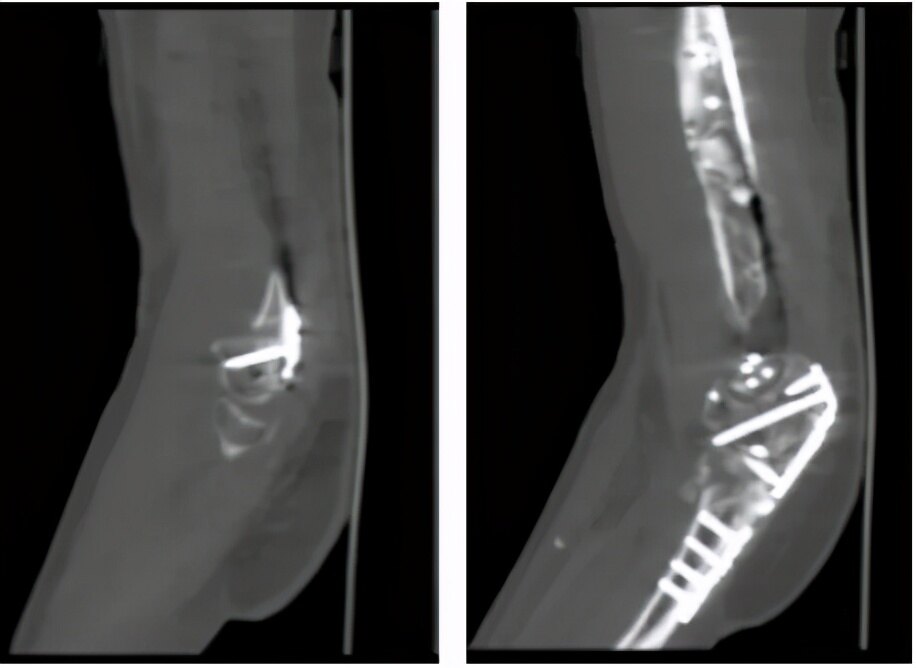

第二次手术-骨折翻修:

肱骨远端外后侧钢板阻挡尺骨鹰嘴滑动

肱骨小头复位不佳

内固定拆除后:

肱骨远端C3型骨折

部分骨质缺损

经过上述三次分期手术,患者骨折复位良好,经过积极的康复锻炼,肘关节功能基本恢复正常。

(术后一个月,CT显示骨折复位情况)